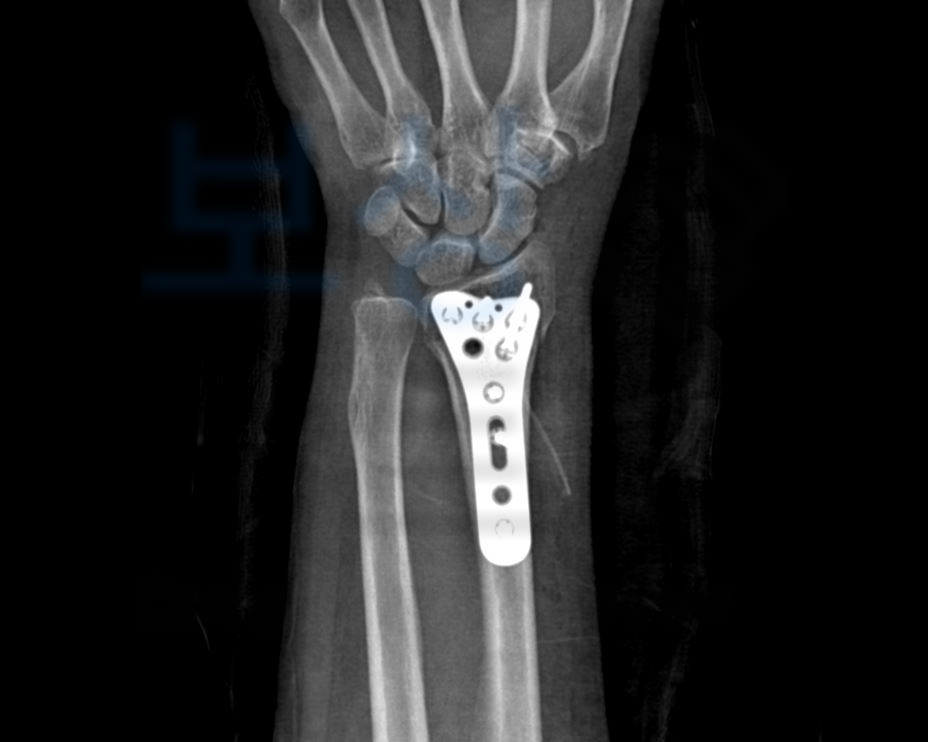

김@@님은 과거 손목 골절을 당하셨고 최근 복사의 골절 진단도 받아 두 부위 모두 금속으로 고정 수술을 받으셨습니다.

** 보통 손목골절은 위의 응급기록지처럼 넘어지며 손을 땅에 짚어 발생된 콜리스골절 (colles fracture)의 형태로 진단되어 수술을 받게 됩니다. 후유장해 보험금 청구를 알아보시다

손목 관절의 약간의 장해 5%